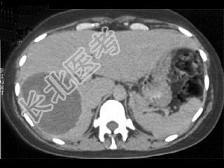

- 单项选择题患者40岁,女性, 肝区偶然发现一个团块,结合图像, 最可能的诊断是 ( )

A、阿米巴肝脓肿

B、肝包虫囊肿

C、肝癌

D、皮样囊肿

E、肝囊肿